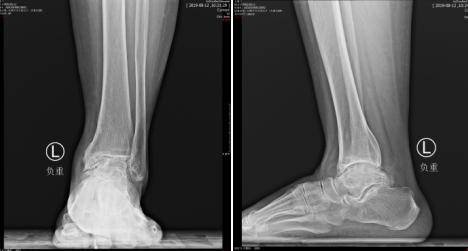

30岁的张师傅是新沂窑湾镇的一个农民。2018年4月,张师傅在家摔伤导致右足跟肿痛一年多,在当地医院检查显示右跟骨骨折,当时未做手术治疗,仅做了保守治疗。一个月前右足跟疼痛加重,X线片显示右跟骨陈旧性骨折,骨折端畸形愈合。张师傅从预告中知道俞教授要来,提出请俞教授做这个手术。俞教授坐诊时,与我院曹广超主任手术团队一起为张师傅做了右跟骨截骨矫形+距下关节融合术。

“手术中,医生把跟骨外侧膨出的骨头削掉,恢复它的长度、宽度与高度,把距下关节给它融合,摆正后足的力线。这样,以后在走路过程中,疼痛会有很大缓解。患者跟骨骨折后没引起重视,保守治疗1年半后,发现一直肿痛,走路疼得厉害没法长时间走,来到咱们医院,检查这是陈旧性骨折,必须通过手术才能解决症状,患者家属也有强烈手术意愿。患者知道俞教授这个月来仁慈坐诊,主动预约,顺利做了手术。”手术小组的赵亮医生说。